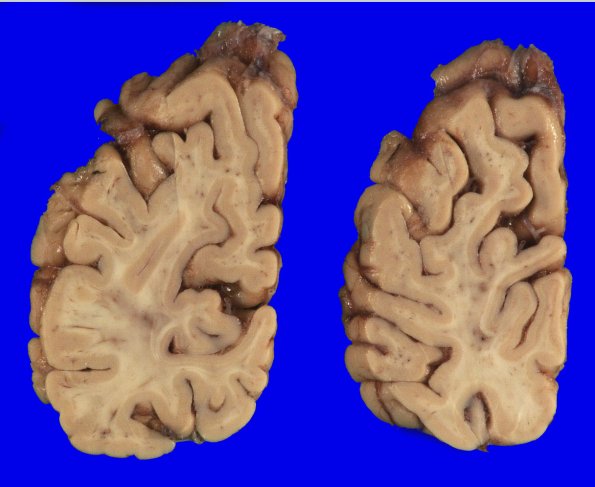

Washington University Experience | NEURODEGENERATION | Argyrophilic Grain Disease (AGD) | 5A6 (Case 5) Gross_6

5A6 (Case 5) Gross_6

At this level there is mild atrophy.